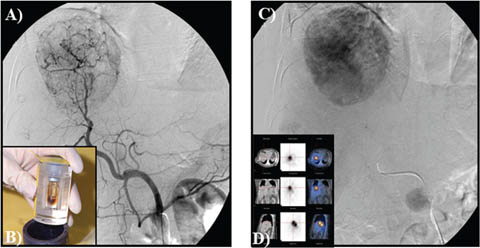

Trans-arterial chemoembolization

TACE is currently the standard of care for patients with intermediate–stage HCC with preserved liver function (7880). TACE is useful for patients that have a Child-Pugh score A or B with tumor diameter of >4 cm or four or more tumors as well as those with single tumor in which it is challenging to carry out liver resection or locoregional therapies as a result of systemic co-morbidities or anatomical limitations (81). TACE takes advantages of the dual arterial and portal venous liver parenchymal blood supply with preferential arterialization not only in cirrhotic liver but of HCC. It involves the selective arterial embolization with a gelatin mixed with lipiodol (a radiopaque contrast agent) with or without chemotherapy (doxorubicin, cisplatin or mitomycin C), into the tumor’s feeding blood vessel (66). The blockage of the arteries supplying the tumor results in tissue necrosis (Figure 10) (68, 79). In practice, TACE is a recommended therapy for patients with unresectable HCC, nonvascular invasion or disease outside the liver (64). TACE can also be used with drug-eluting beads (DEB-TACE) and evidence exists that patients who are on DEB-TACE treatments for unresectable HCC have better performance in comparison to those on conventional TACE (66). In addition, TACE is being used for the downstaging of tumors in association with systemic therapy or as bridge for transplantation.

Fig 10

Figure 10. Trans-arterial chemoembolization of the liver for hepatocellular carcinoma. A and B. Selective arterial embolization of the vessels feeding the tumor in the liver. C. Tumor visualized by CT scan. The procedure is performed with or without chemotherapy. D and E. After embolization, angiography showed obliteration of feeding vessels with shrinkage of the tumor. F. Follow up CT scan after embolization. Note an increase in patient’s ascites.